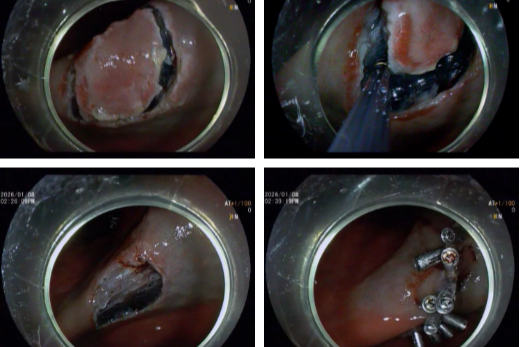

为重度主动脉瓣狭窄患者完成微创 「换心门」! 镇江瑞康医院成功开展 TAVI 术